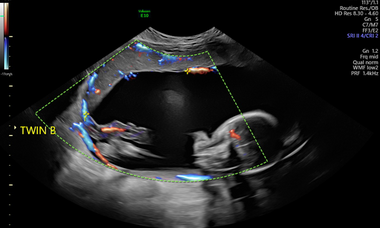

The December issue of Ultrasound in Obstetrics & Gynecology includes an observational cohort study assessing the neurodevelopmental outcomes of uncomplicated monochorionic diamniotic twins, a systematic review evaluating the use of twin vs singleton growth charts for identifying small-for-gestational-age fetuses at risk of adverse neonatal outcomes, a study investigating the performance of non-invasive prenatal testing in vanishing-twin and multiple pregnancies, and a prospective cohort study examining the prevalence of LAM avulsion after forceps-assisted and vacuum-assisted deliveries.

December is International Twin-Twin Transfusion Syndrome (TTTS) Awareness Month - a time to recognise a life-threatening complication that affects 9-15% of monochorionic pregnancies.